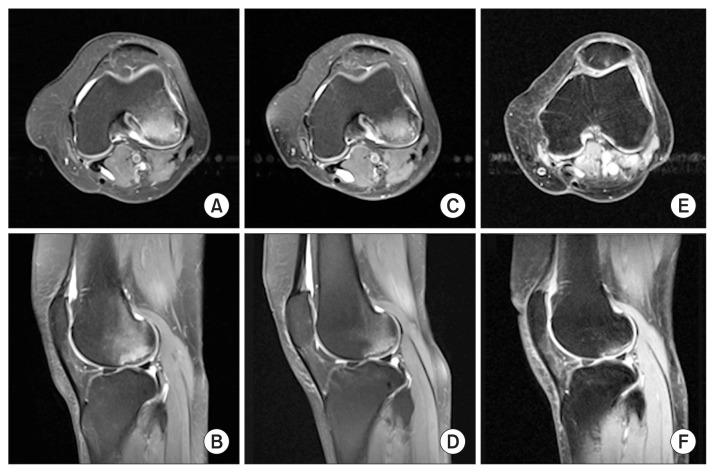

A 64-year-old marathon runner presented to our clinic with a history of worsening pain in her left knee. Following magnetic resonance imaging, the diagnosis of subchondral insufficiency fracture of the knee (SIFK) was made. A course of conservative management via bisphosphonates was initiated. The patient successfully recovered and returned to full athletic function, having recently returned to competitive marathon running. This article aims to present this unusual case of lateral compartment SIFK and summarise the literature on this uncommon condition.

一名64岁的马拉松运动员因左膝疼痛加重前来我院就诊。经磁共振成像检查后,诊断为膝关节软骨下不全骨折(SIFK)。开始了通过双膦酸盐进行的保守治疗疗程。患者成功康复并恢复了全部运动功能,最近已重返马拉松比赛。本文旨在介绍这例罕见的外侧间室SIFK病例,并总结关于这种罕见病症的文献。